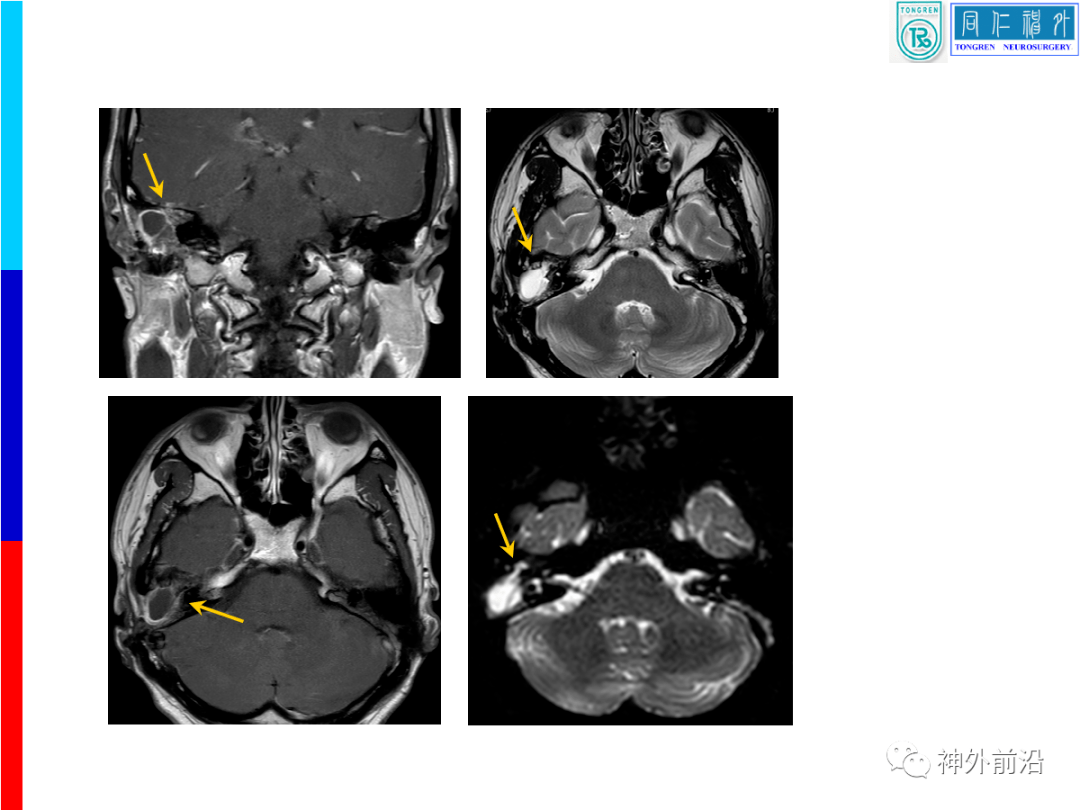

同仁颅面创伤容易误诊的脑脊液耳漏如何手术治疗康军

图片尺寸1080x810